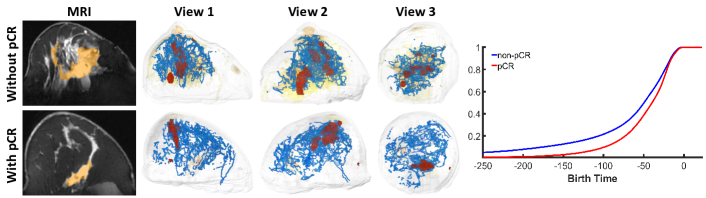

Fig. 7 presents topological structures from three distinct perspectives, showcasing one representative sample each for cases with and without pCR. We observe that the 1D and 2D structures are sparser in the case with a pCR response, while they appear denser in the non-pCR case. Examining the corresponding MRI images, we notice that the breast with pCR exhibits scattered fibroglandular tissue and minimal background parenchymal enhancement. In contrast, the non-pCR breast displays more heterogeneous fibroglandular tissue accompanied by moderate background parenchymal enhancement. This observation suggests that the topological structures may be capturing the intricate fibroglandular structure, potentially serving as an indicator of treatment response.

We also analyze the topological characteristics of two patient populations by comparing their birth times, which indicate the threshold at which a cycle first appears. Given our use of the inverse image in the experiments, denoted as , meaning the birth time essentially corresponds to times the brightness of a structure. For each population (pCR and non-pCR), we compute the Cumulative Density Function (CDF) curve using the average birth time from all samples in that group. As depicted in Fig. 7 (right), the CDF for pCR patients (in red) compared to non-pCR patients (in blue) reveals that topological structures in pCR patients’ tissues tend to be less bright or distinguishable than those in non-pCR patients, an observation that aligns with our qualitative assessments. To statistically validate these differences in CDFs, we conduct a Kolmogorov-Smirnov test [45]. The resulting -value of indicates a significant disparity in the birth time distributions between the pCR and non-pCR patient groups.